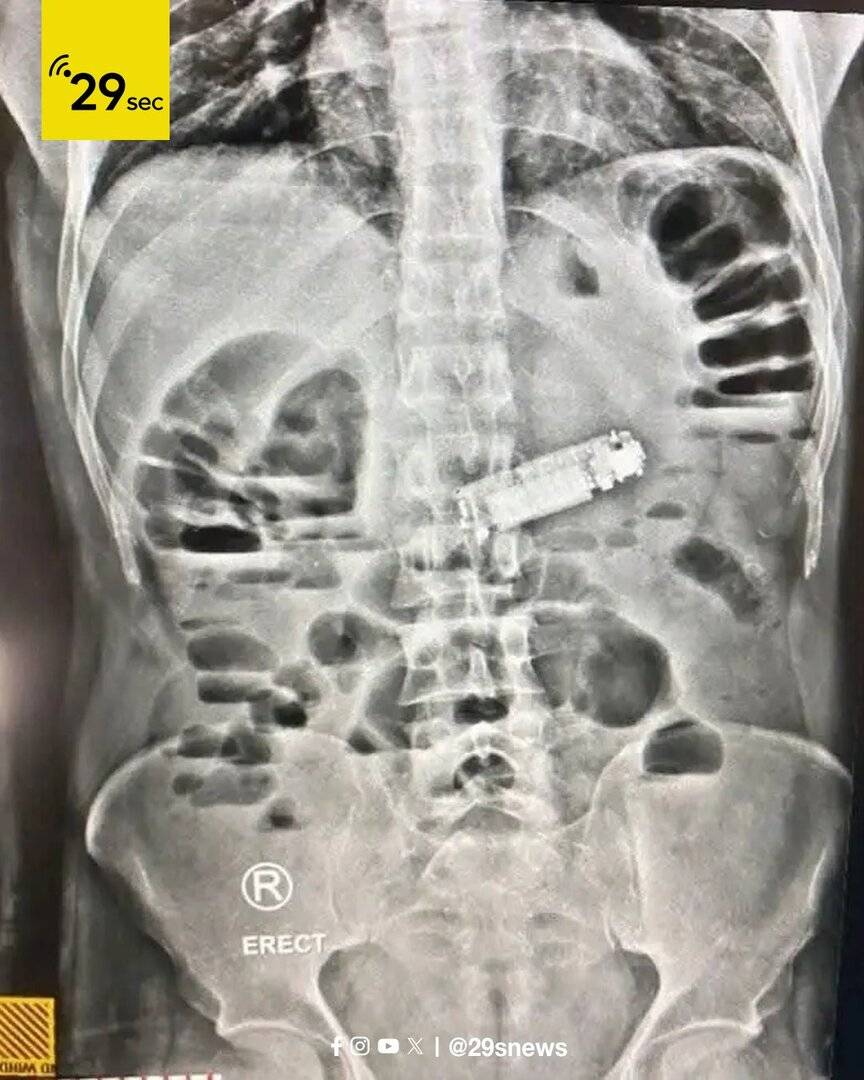

فريق طبي مصري يستخرج هاتفا من معدة مريض (صور)

نجح فريق طبي متخصص في مستشفى الغردقة العام بمصر في إجراء عملية جراحية عاجلة لاستخراج هاتف محمول صغير ابتلعه أحد المرضى، بعد أن تسبب في انسداد فتحة البواب بالمعدة وحدوث أعراض حرجة.

وأوضحت مديرية الصحة بالبحر الأحمر أن المريض وصل إلى المستشفى في حالة حرجة يعاني من إعياء شديد، وقيء مستمر، وآلام حادة في البطن.

وبعد إجراء الفحوصات الطبية والأشعة اللازمة، تم الكشف عن وجود جسم غريب يسبب انسدادا في فتحة البواب في المعدة، وهو الهاتف المحمول.

عقب ذلك قام الفريق الطبي بإجراء العملية الجراحية الدقيقة، وتمكن من استخراج الهاتف بنجاح ودون مضاعفات، حيث استعاد المريض وعيه في قسم الإفاقة، وحالته الصحية مستقرة، ويخضع حاليا للملاحظة الطبية.